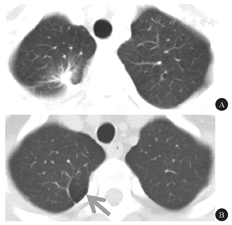

患者1 男性,28岁,因"左侧面部过度出汗伴潮红3 d"于2020年6月11日入院。患者既往有右肺大疱切除术病史6年,术后10 d复查胸部CT平扫提示右上肺炎症。体检:以头面部正中线为界,左侧面部大汗淋漓伴皮肤潮红,右侧皮肤皮色正常、无汗,且无其他阳性体征(图1)。辅助检查:血常规、甲状腺功能、肝肾功能、电解质、血糖、免疫四项等均未见异常。甘油三酯2.56 mmol/L(↑),尿酸442.7 mmol/L(↑)。颅脑MRI平扫+MRA未见明显异常。颈椎MRI平扫示轻度退行性改变。胸部CT平扫示,与既往胸部CT结果比较,双肺纹理增多,右肺上叶(T2~3椎体处)一新发肺大疱(图2)。颈动脉彩超、甲状腺彩超未见异常。入院后予以谷维素调节植物神经、抗炎治疗,症状无明显改善,要求自动出院。出院后3个月时随访,患者每次运动、情绪激动时仍反复出现上述症状,但无其他不适主诉。

A:2014年;B:2020年(箭头示新发肺大疱)